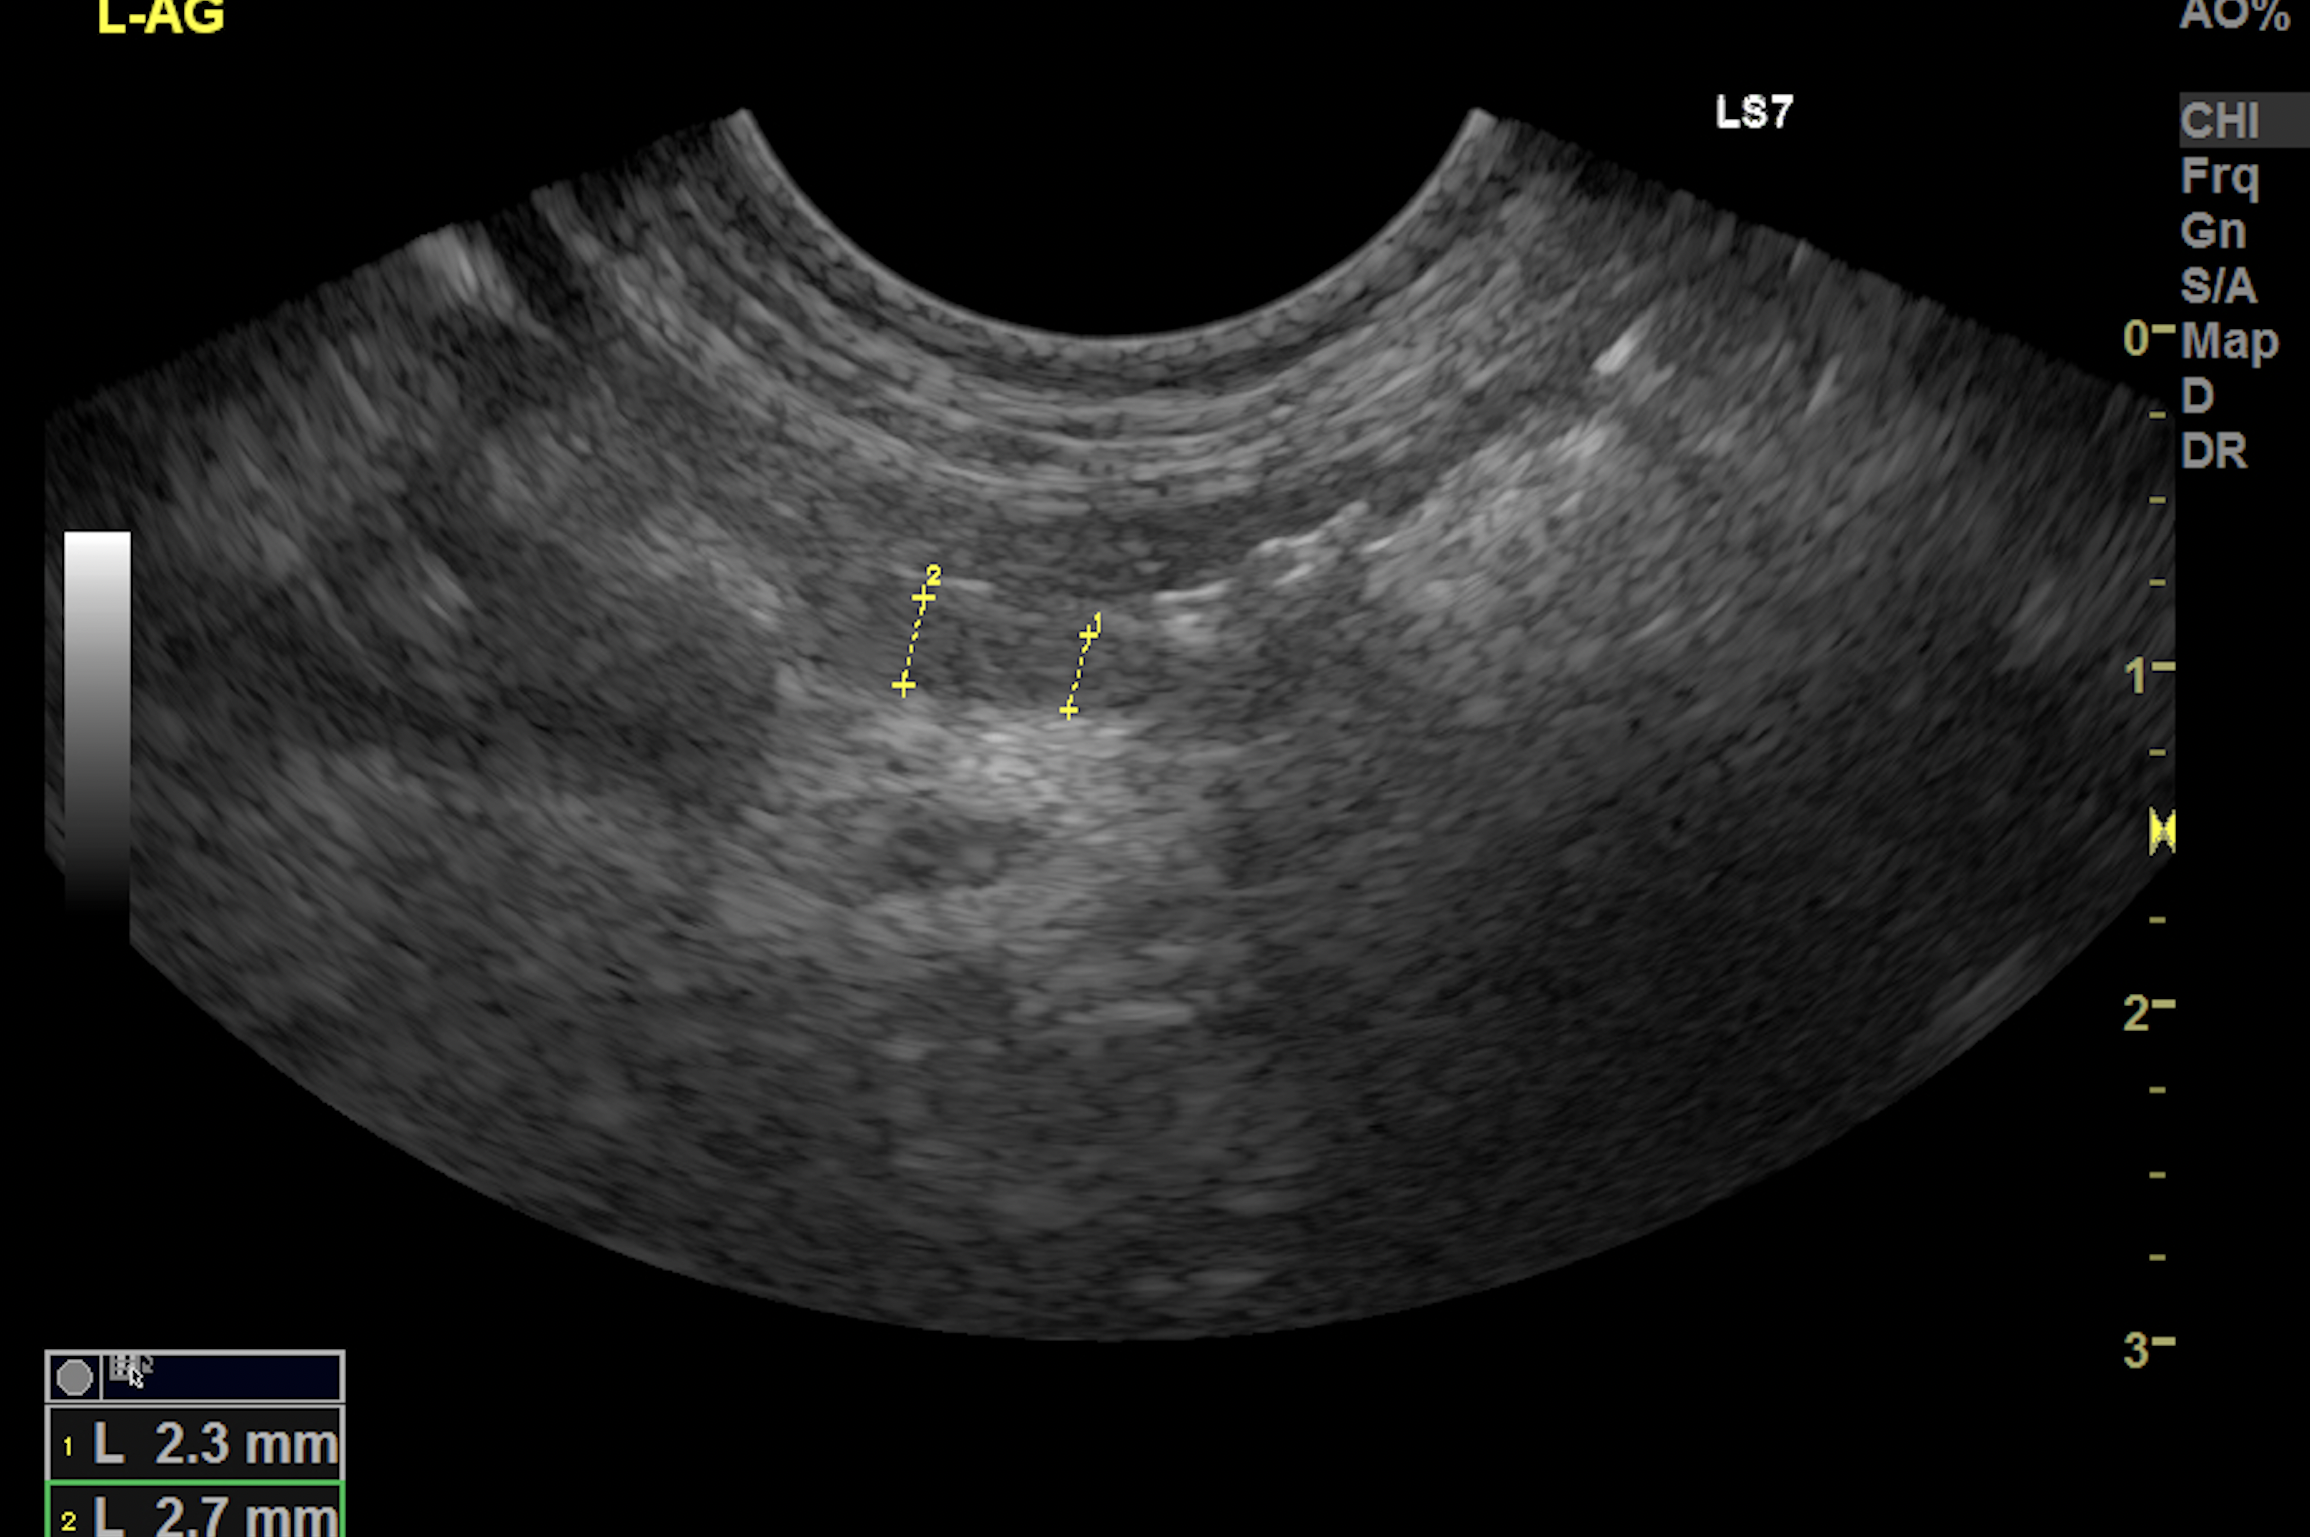

超音波画像(小さいサイズの副腎)

当院では、超音波検査で、副腎の大きさが3ミリ以下であれば、疑います。確定はホルモン検査になります。